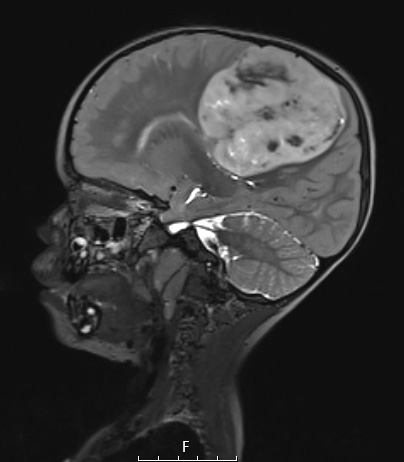

8A4 ETMR (Case 8) T2W - Copy

The image is patchy hyperintense in this T2-weighted image as seen in this sagittal scan.